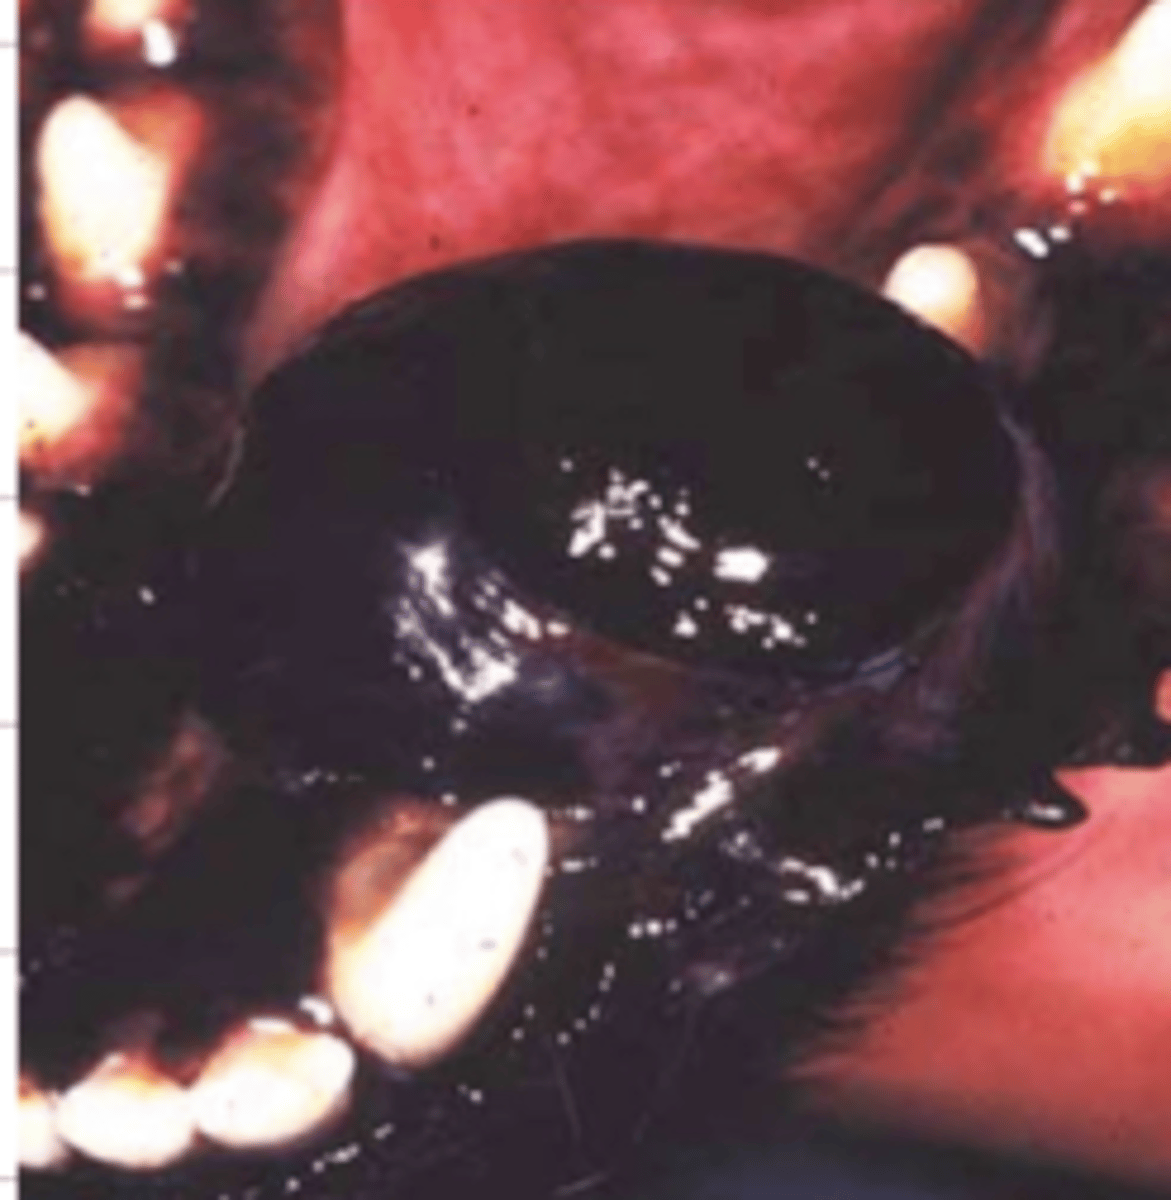

malignant melanoma

it is very aggressive and painful, and is the most common neoplasia in the mouth of dogs

what is this?